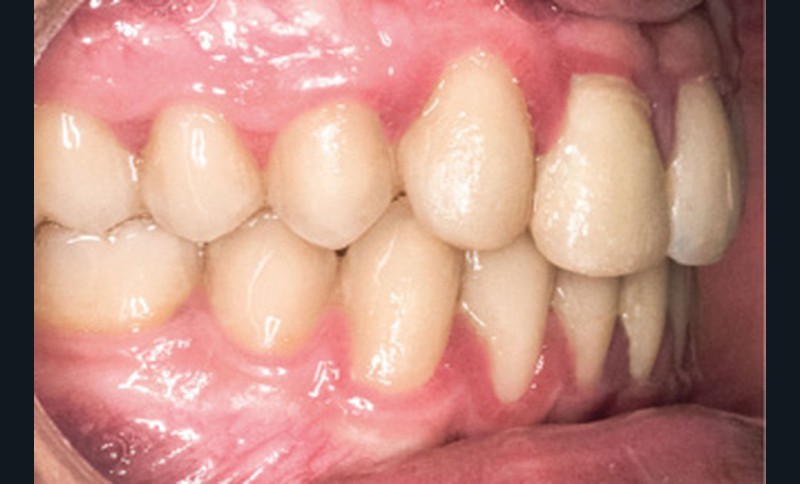

D’un point de vue occlusal, le patient, en denture adulte jeune stable, présente une classe II d’Angle bilatérale de 4 mm, associée à un encombrement maxillaire de 5 mm et mandibulaire de 2 mm. La face mésiale de 21 est centrée avec le plan sagittal médian, la non-concordance des médianes incisives est d’origine mandibulaire (déviation de la médiane mandibulaire vers la gauche) (fig. 1b-d).